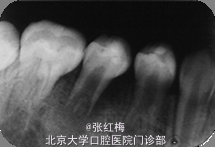

45牙合面充填体完好,边缘密合,叩痛(+),松I0,冷热测均无反应,舌侧牙根对应粘膜见1×1.2cm2 脓包扪诊有波动感,X线:发育8-9期,根中下1/3分成两根,根尖孔喇叭状,根尖周低密度影。

在牙髓再生术后1个月,3个月,5个月,9个月复查 1个月x线:45根尖周低密度影缩小,牙根继续发育。 3个月x线:45根尖周未见病变影,根周膜清晰,牙根继续发育。 5个月x线:45根尖周未见病变影,根周膜清晰,牙根继续发育。 9个月x线:45根尖周未见病变影,根周膜清晰,牙根继续发育,已近完成,髓腔缩小。 讨论:由于畸形中央尖一部分有髓角伸入,因此发现畸形中央尖应根据不同情况给予及时或相应处理。对于圆钝而无妨碍的中央尖可以不做处理。尖而长的中央尖容易折断或被磨损而露髓.可在麻醉和严格消毒下将此尖一次磨除。制备洞形,盖髓充填。还有一种方法树脂在牙尖周围加固防折,使畸形尖随牙齿一同发生生理磨耗,促使髓角形成修复性牙本质,可用于尚未建合的牙。短期内折断的畸形中央尖无牙髓根尖炎症状,且牙髓活力正常者,备洞盖髓充填。折断的畸形中央尖有牙髓炎根尖炎者,往往牙根未发育完成,需做根尖诱导形成术,或牙髓再生治疗。 牙髓坏死或者根尖炎年轻恒牙的牙髓治疗方法有:根尖诱导成形术,MTA根尖封闭技术,近年来的牙髓再生技术。 根尖诱导成形术,所用根管内充填材料是氢氧化钙及其制剂,诱导根尖周的组织在根尖部形成钙化屏障。需要多次复诊和更换根充药物,疗程较长,增加了根管再次污染的可能性,并不是所有都能形成根尖部的钙化封闭。而且根管壁仍然薄弱,增加了远期根折的风险。 MTA具有良好的生物相容性和封闭性,MTA根尖封闭技术中用其特性封闭根尖,防止充填材料在根尖部的外溢。生物相容性好,可以诱导矿化,但其完全固化需要较长时间,不易操作,抗菌效果不确定,价格昂贵。 牙髓血管再生术通过在操作中彻底有效的根管消毒,尽量保护牙髓干细胞和牙乳头间充质干细胞,并为这些干细胞的增殖和分化提供良好的环境,这些干细胞在信号分子和盖髓剂矿物三氧化物凝聚体(mineral trioxide aggregate,MTA)的诱导下,可以分化为成牙本质细胞和成牙骨质细胞等,从而在牙根继续发育中发挥着重要作用。研究表明,在坏死感染的年轻恒牙根管内进行成功的血管再生后,其根尖周炎症能愈合且牙根得以持续发育,出现根尖闭合、根管长度增加及管壁增厚等,牙髓血管再生术有可能成为治疗年轻恒牙根尖周炎的新选择。